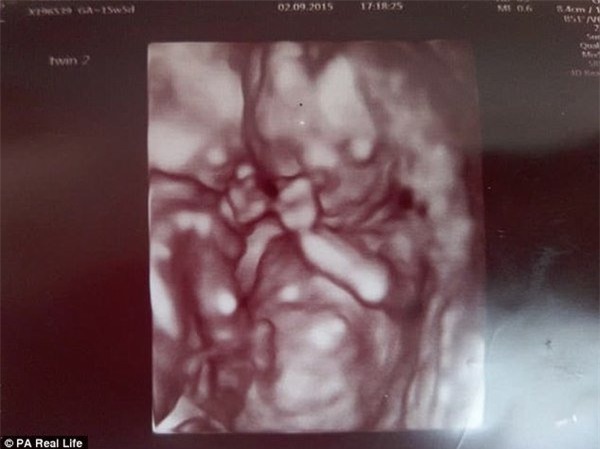

Thế nhưng, một điều kì diệu đã xảy ra khi Vicky đi siêu âm vào tuần thứ 12 của thai kỳ. Trên màn hình siêu âm, hai bé trai trong bụng cô đã di chuyển đến một tư thế an toàn cho cả hai, khiến sợi dây rốn khó có thể rối vào nhau được, đó là tư thế ôm lấy nhau. Đồng thời, tư thế này cũng giúp hai bé có được nhiều không gian phát triển nhất có thể.

Hình ảnh diệu kỳ khi hai bé Reuben và Theo ôm lấy nhau trong bụng mẹ, nhờ đó, cùng nhau thoát khỏi lưỡi hái tử thần

Đối với tất cả những người có mặt tại phòng siêu âm khi ấy, đây thực sự là một điều kỳ diệu. Tâm sự với mọi người, Vicky cho rằng có lẽ tình cảm anh em đã khiến hai bé bảo bọc lấy nhau ngay từ trong bụng mẹ một cách rất bản năng "Vì chúng thậm chí còn biết nhau trước khi biết được rằng cuộc sống thực sự là gì".